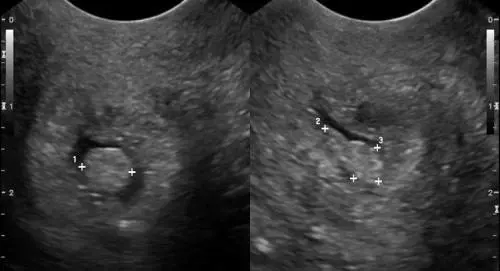

Se le dimensioni della massa tumorale superano i quattro centimetri di diametro, l'unica strategia terapeutica è quella chirurgica

L’ecografo è più attendibile ed è facile e veloce. In un'ora e mezzo si possono fare anche 25-30 esami

Se provocano sintomi o se di grosse dimensioni, queste escrescenze devono essere rimosse chirurgicamente